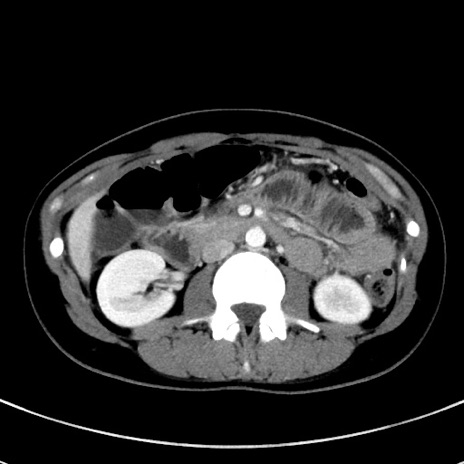

症例17(横断像)

【症例】20歳代女性

【主訴】嘔吐、下腹部痛

【現病歴】昨日夕食後に嘔吐し下腹部痛が出現。本日になっても嘔吐持続し改善しないため来院。

【身体所見】意識清明、BT 37.2℃、BP 108/67mmHg、腹部:平坦、やや硬、下腹部正中から右にかけて圧痛あり、反跳痛軽度あり、tapping pain(+)。

【データ】WBC 13600、CRP 14.94